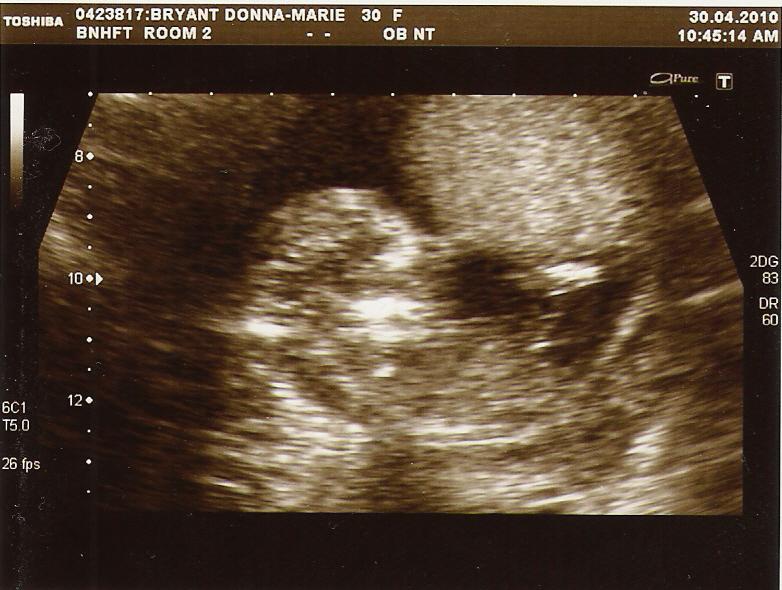

Nuchal Scan

I was in such pain today after our nuchal scan, the woman who performed it was really rough and quite abrupt which somewhat spoilt what should have been a beautiful and special milestone for us.

Never the less we have been able to see "the bean" jumping and diving about inside me now, 2 arms, 2 legs and all the right bits in between and have been told that our chance of a Downs baby is minimal.